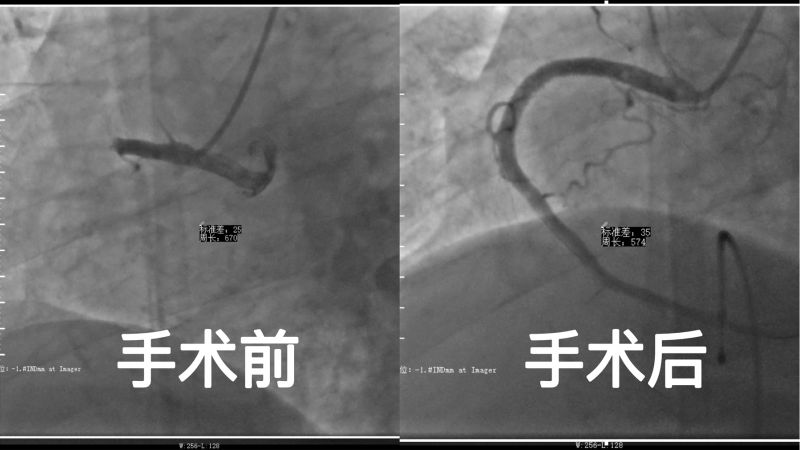

8月20日,胡奶奶被诊断为急性心肌梗死后,转入烟台山医院东院区治疗。入院时,胡奶奶胸骨后持续剧烈疼痛,伴胸闷、喘憋、头晕,心电图显示三度房室传导阻滞,心率38次/分。高敏肌钙蛋白I:28.65ng/ml,前脑利钠肽:16131.00pg/ml,肾功:血肌酐247.7umol/l。值班医师康浩飞主治医师立即急诊启动导管室。造影显示冠状动脉分布呈右优势型,右冠脉近端完全闭塞。由于患者病情危重,加之高龄、肥胖(体重220斤),术中心衰烦躁不配合,血管入路严重迂曲,手术难度非常大。刘文波副院长带领杨芳主任、李菲副主任、康浩飞主治医师,制定治疗方案,在导管室护士、技师的通力配合下,克服重重困难,顺利为患者进行了临时起搏器植入术+支架植入术。手术顺利完成,术后经精心照护,胡奶奶恢复良好。